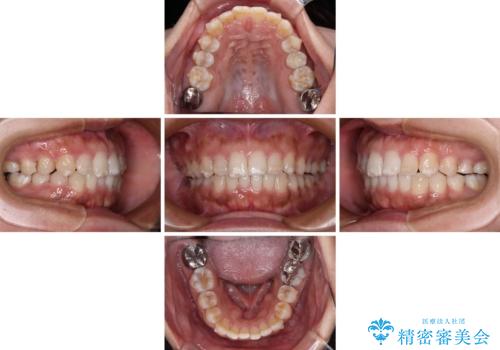

- 上下前歯の叢生を気にして来院された患者様です。

軽度な叢生であり、安価で短期間の治療を規模されていたため、インビザライン・モデレートを用いて矯正治療を行うこととしました。

インビザライン・モデレートは、製作できるアライナーの枚数に制限があるため、移動可能な量に限りがあるものの、インビザライン・ライトよりも枚数が多いため、幅広い症例に対応可能です。